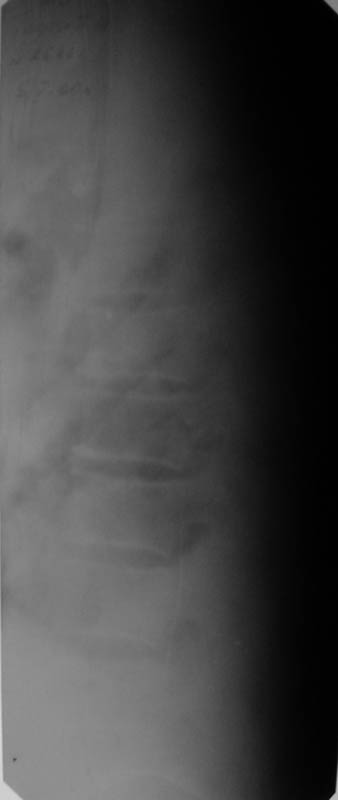

Мужчина, 48 лет. 8.04. 2000 г. - сочетанная травма: компрессионные переломы тел Th4- Тh6 и L1 позвонков с синдромом полного нарушения проводимости спинного мозга -

нижней параплегией, нарушением чувствительности и функции тазовых органов; переломы III-IV ребер справа,VI-VII ребер слева со смещением,травматический немопневмоторакс слева, гемоторакс справа, оскольчатые переломы обеих лопаток со смещением, перелом правой ключицы со смещением, тупая травма живота, ушиб сердца. Осложнения:посттравматическая пневмония, посттравматический плексит справа, цистит, пролежень в области крестца.

В настоящее время жалобы на отсутствие чувствительности в нижних конечностях, невозможность самостоятельной ходьбы (передвигается на кресле).КОНСУЛЬТАТИВНОЕ ЗАКЛЮЧЕНИЕ ЯМР-ТОМОГРАФИЧЕСКОГО ИССЛЕДОВАНИЯПроведена МР_томография грудного отдела позвоночника в сагиттальной проекции, с различной степенью контрастирования тканей, в режимах Т1 и Т2 В/И + МР-миелоурография. Визуализированы: спинной мозг с уровня D1 до уровня D12, тела позвонков D1-D12, межпозвонковые диски. Спинной мозг на уровне D4-D6 истончен с неровными нечеткими контурами, гетерогенной структуры, умеренно пониженной интенсивности на Т1 В/И, без очаговых изменений. Отмечается клиновидная деформация тела D5, снижена высота тела D4, структура его гетерогенная. Обращают внимание выраженные дегенеративные изменения дисков в грудном отделе позвоночника: снижение их высоты, изменение структуры изображения за счет исчезновения высокоинтенсивного сигнала от ядер. При исследовании в режиме МР-миелоурографии ликворный сигнал на уровне D4-D5 почти прерывается, интенсивность его существенно снижена.

ЗАКЛЮЧЕНИЕ: ПОСЛЕДСТВИЯ КОМПРЕССИОННОГО ПЕРЕЛОМА ТЕЛА D4-D5 С КОМПРЕССИЕЙ СПИННОГО МОЗГА. МРТ-ПРИЗНАКИ МИЕЛОПАТИИ И РУБЦОВО-СПАЕЧНОГО ПРОЦЕССА В ПОЗВОНОЧНОМ КАНАЛЕ НА УРОВНЕ D4-D5. ВЫРАЖЕННЫЕ ДЕГЕРАТИВНЫЕ ИЗМЕНЕНИЯ ДИСКОВ В ГРУДНОМ ОТДЕЛЕ ПОЗВОНОЧНИКА.

Уважаемый коллега, для решения о тактике дальнейшего ведения , необходимо иметь более детальную неврологическую картину - с какого сегмента идут расстройства чувствительности( какие виды чувствительности выпали), т.к если я не ошибаюсь у больного есть еще перелом L1 - на снимках его не видно.